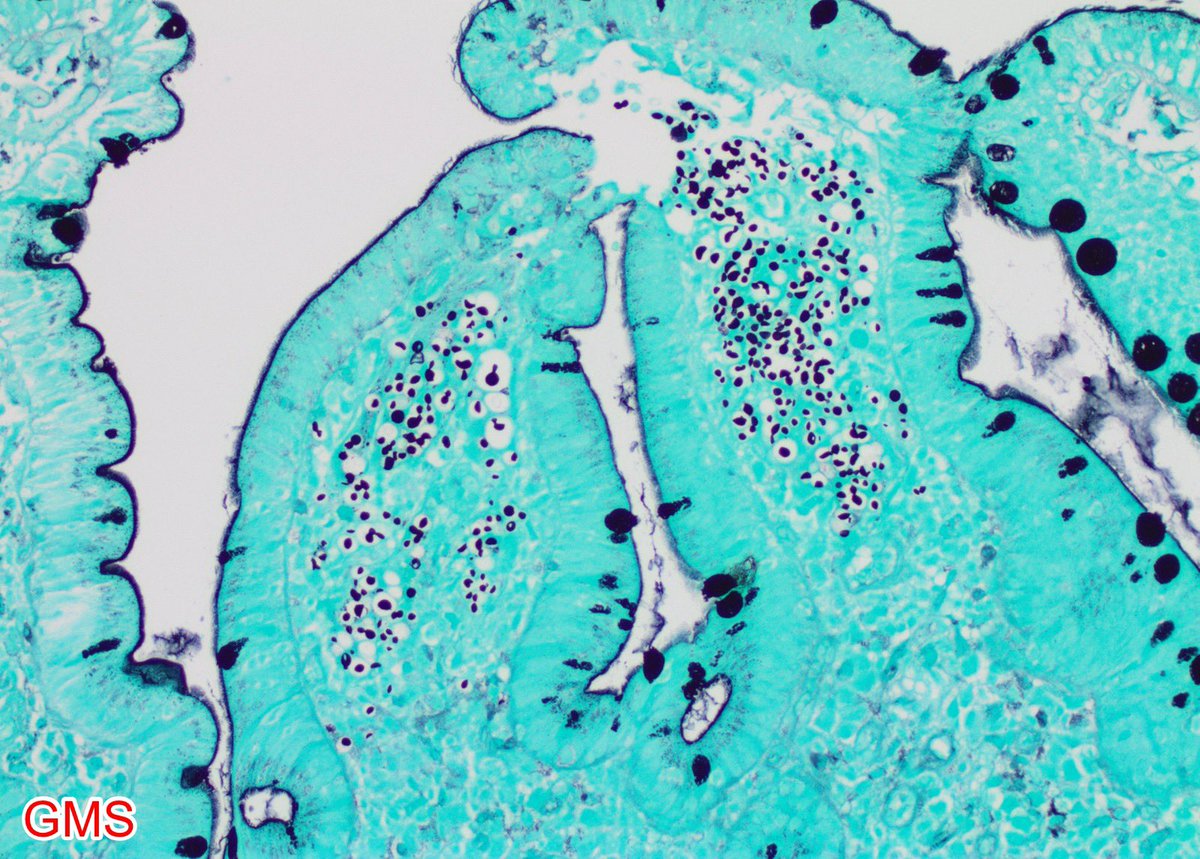

Duodenal biopsy in an HIV+ pt with chronic diarrhea: 🔬 Cryptococcus – variably sized (3.5 - 8 μm) encapsulated yeasts with narrow based budding highlighted by GMS & Mucicarmine special stains. 🧫 Cryptosporidium – tiny 2–5µm organisms attached to apical enterocyte surface. A